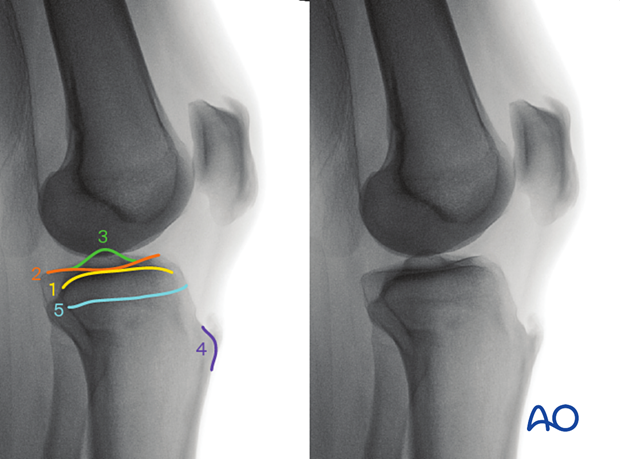

To obtain the optimal lateral view of the distal femur:

The optimal lateral view to the proximal tibia is obtained when:

The following lines and landmarks are seen in the lateral view of the proximal tibia:

The lateral view of the proximal tibia is particularly useful to identify: